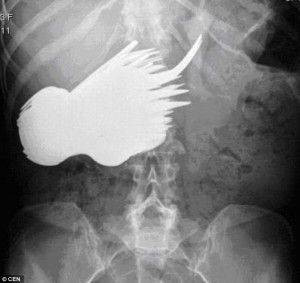

MİDESİNDEN VANA ÇIKTI- Van'da mide ağrısı şikayetiyle hastaneye kaldırılan kadının bağırsağından, 10 santimetre uzunluğunda vana kolu çıktı. Midenin ardından kalın bağırsağa yerleşen cismin doğal yollardan vücuttan atılmayacağını tespit eden doktorlar, hastaya operasyon yapılmasına karar verdi. Yaklaşık 40 dakika süren operasyonda vana kolu bağırsaktan çıkarıldı.